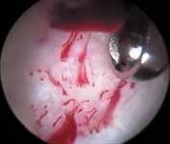

2. Disrupted fibers of the ligamentum teres, whether from trauma or degeneration, can be quite painful, creating soft tissue impingement within the joint.

3.

Associated with this soft tissue impingement, the pulvinar tissue often is hyperplastic or fibrosed and also can create painful symptoms.

4.

Indiscriminate débridement of the ligamentum teres should be avoided and intact fibers preserved; however, débridement of the disrupted portion can be quite beneficial ( TECH FIG 4).

8.

Most of the contents of the acetabular fossa are best accessed from the anterior portal.

9.

However, a portion of the posterior contents often is best accessed with instrumentation introduced from the posterolateral portal.

10.

Between these two sites most pathologic processes can be accessed with combinations of straight, curved, and flexible instruments.

---

A B C TECH FIG 4 • A. Arthroscopic view from the anterolateral portal reveals disruption of the ligamentum teres (

). B. Débridement is begun with a synovial resector introduced from the anterior portal. C. The acetabular attachment of the ligamentum teres in the posterior aspect of the fossa is addressed from the posterolateral portal. (Reprinted with permission from Byrd JWT, Jones KS. Traumatic rupture of the ligamentum teres as a source of hip pain. Arthroscopy 2004;20:385–391.) PEARLS AND PITFALLS Patient selection Patient positioning Portal placement Avoid iatrogenic damage Avoid excessive labral resection Avoid advanced disease states